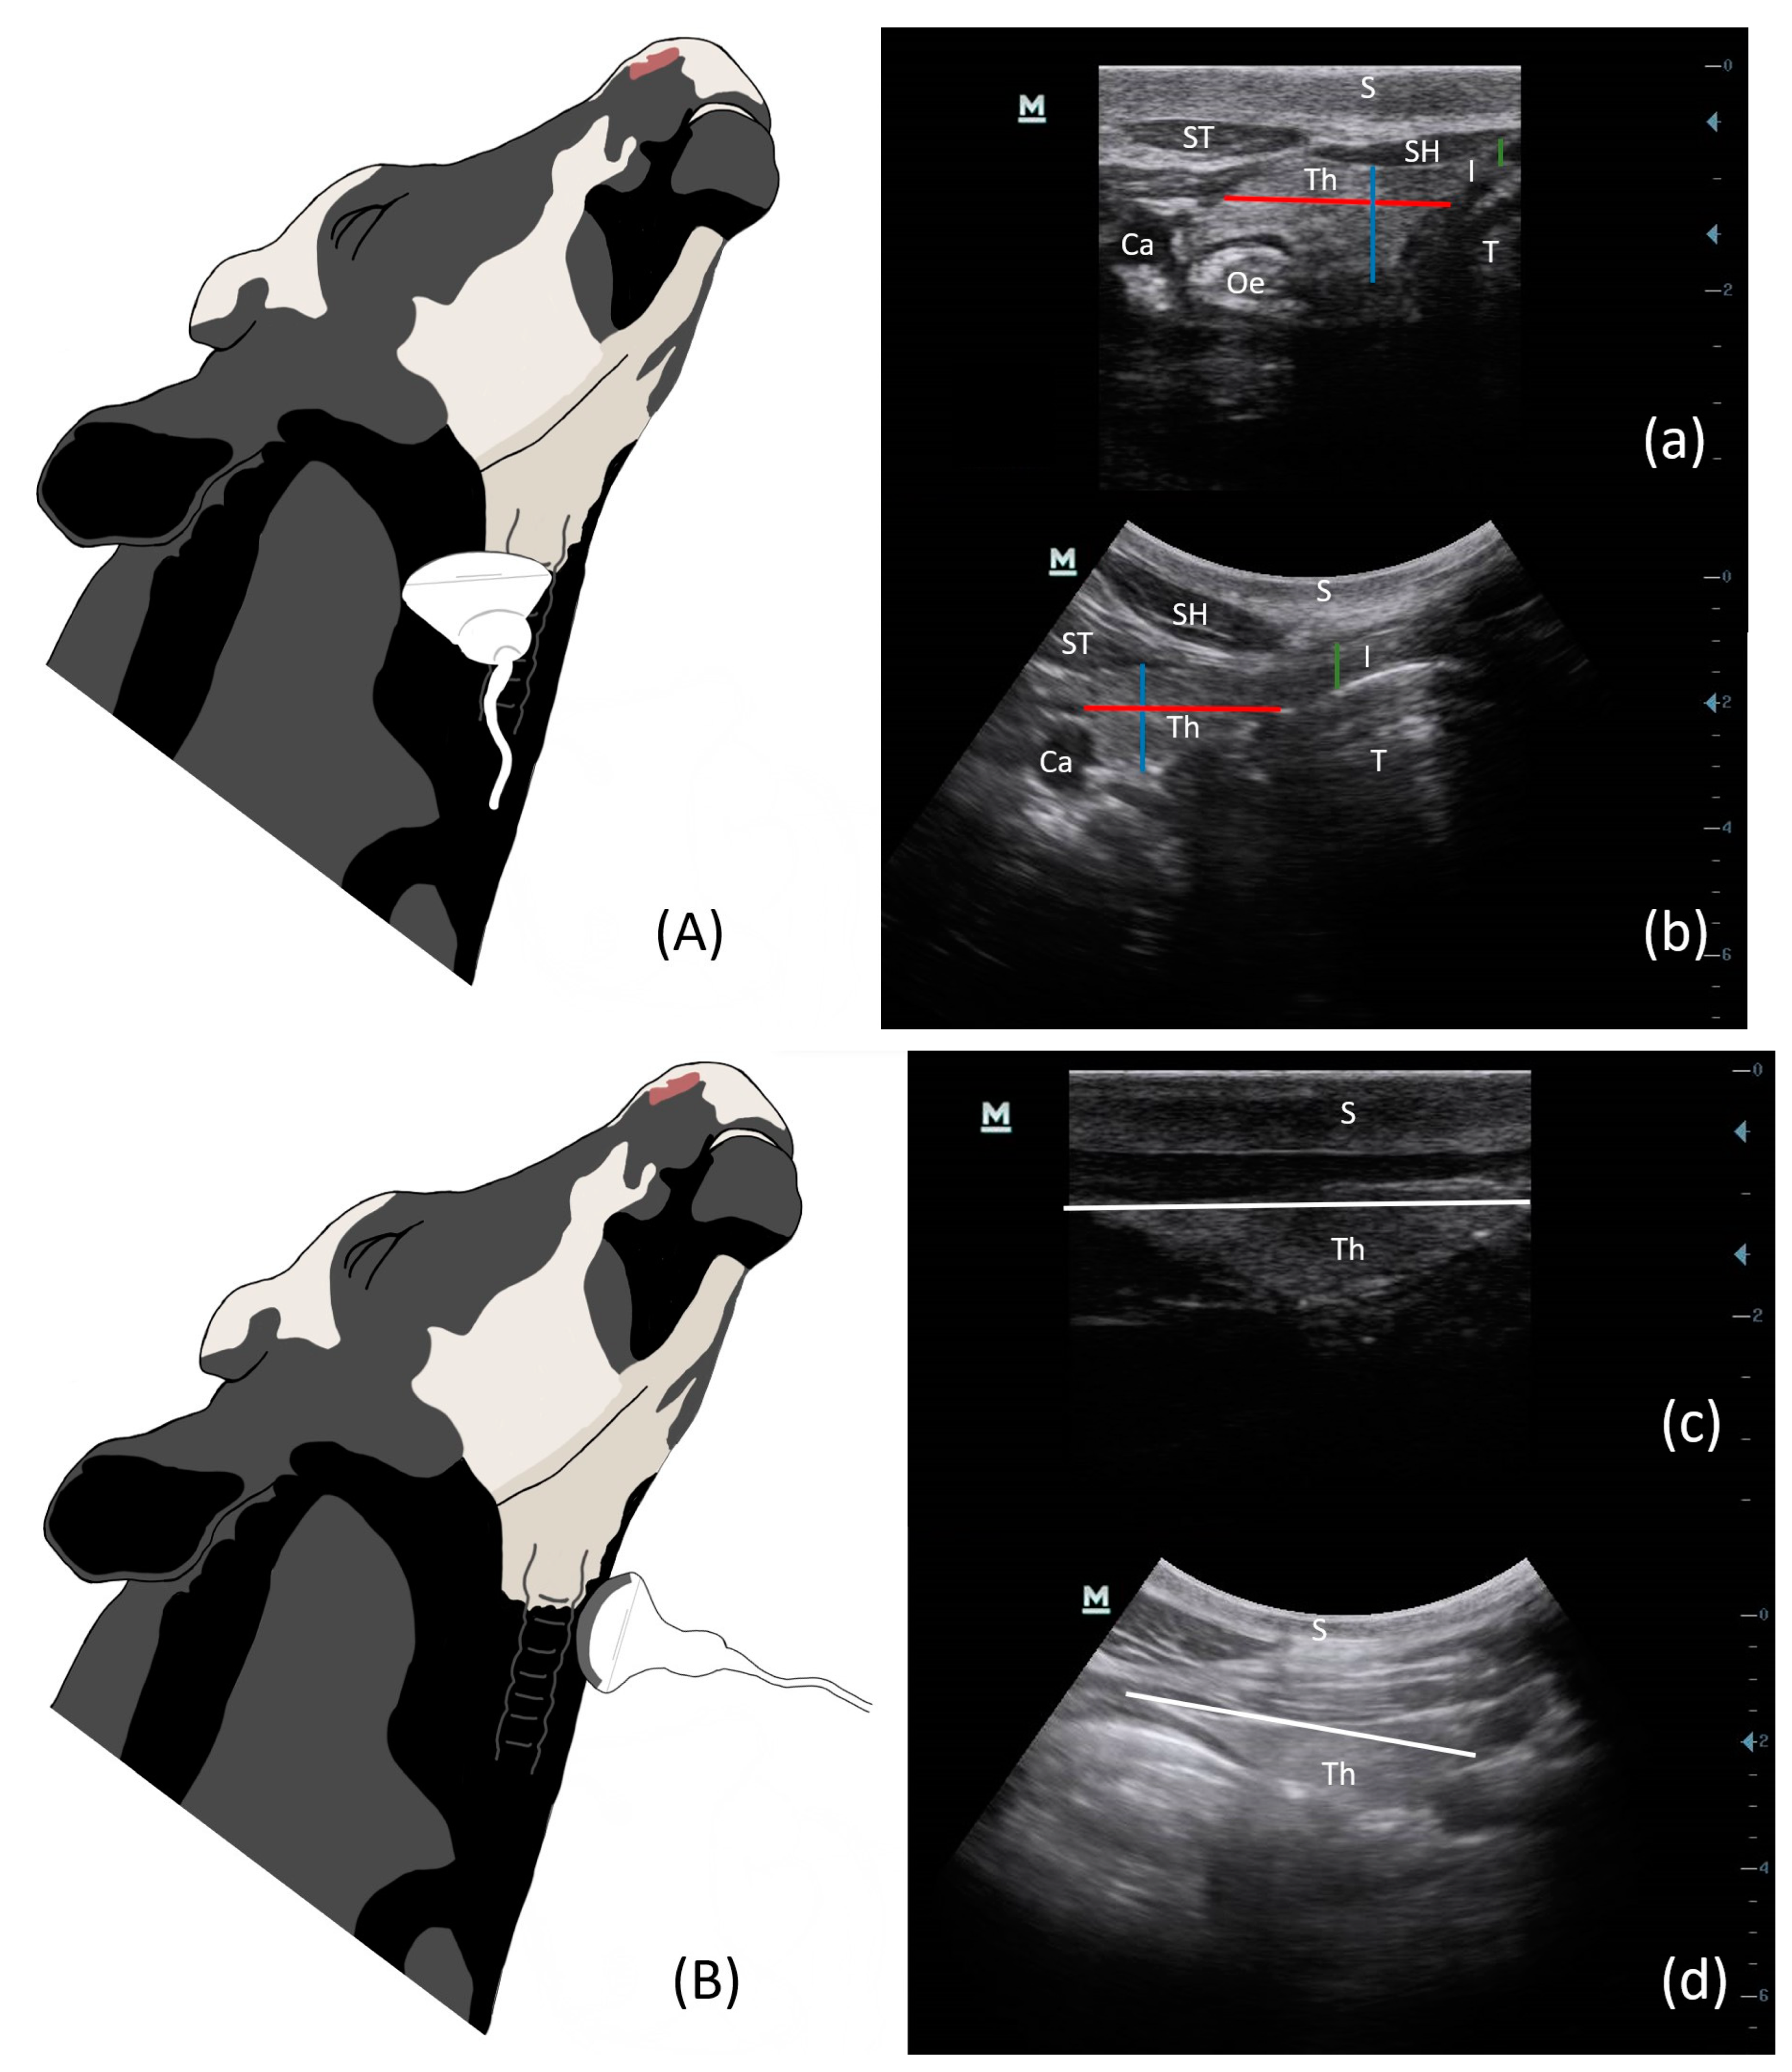

3.1. Ultrasound Technique and Measurements